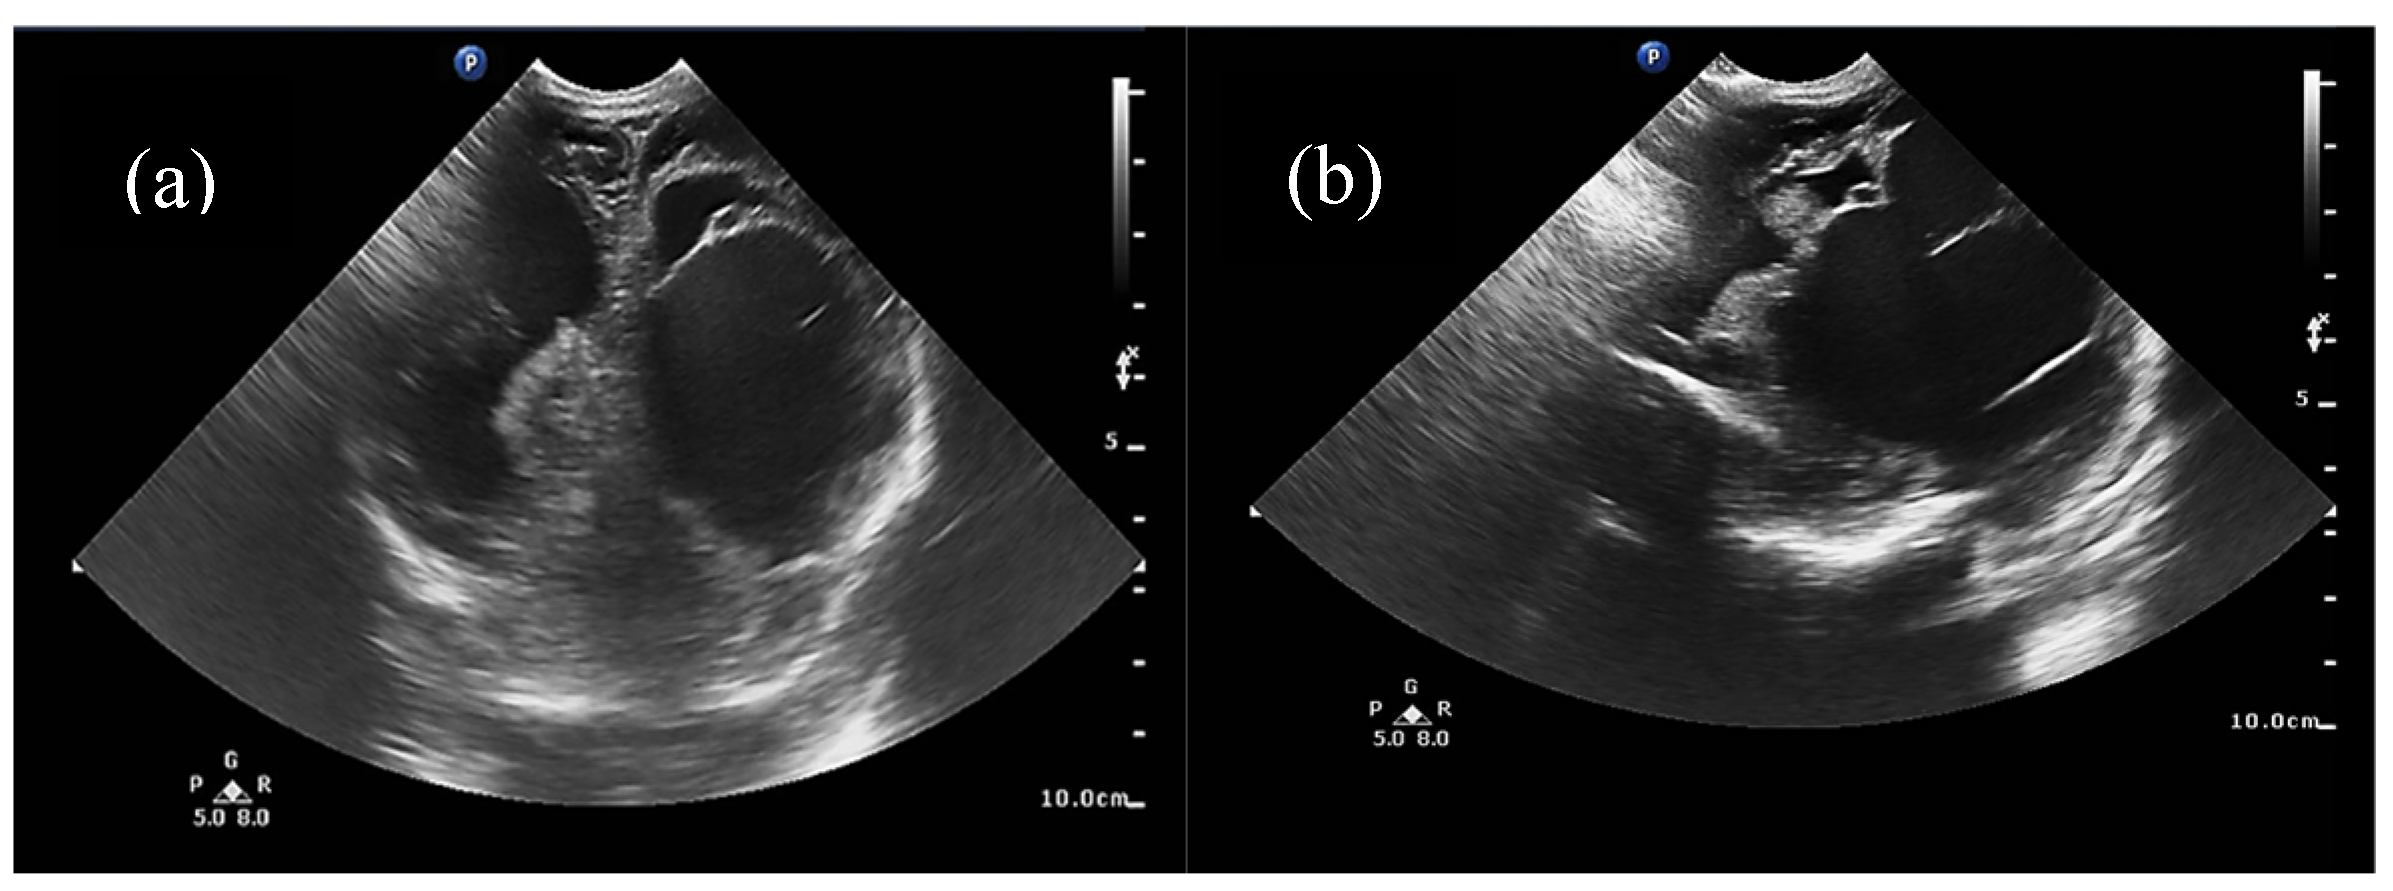

Half of the patients were diagnosed antenatally (by ultrasound or fetal MRI) and half of them postnatally, most frequently by cerebral ultrasound or after auscultation of a cardiac murmur followed by heart ultrasound displaying diastolic steal from the thoracic or descending aorta into the carotid territory towards cerebral circulation. The general aspect described was that of a saccular structure located at the level of the quadrigeminal tank with both arterial and venous Doppler signals, communicating with the large cerebral sinuses and having numerous arterial and venous collaterals (see Figure 1 and Figure 2).

Figure 1. (a) Two-dimensional ultrasound of the VoGM via anterior fontanelle, (b) 2D ultrasound of the VoGM via the mastoid fontanelle. Voluminous, multilobulated, transonic mass of 6/3 cm, exerting a compressive effect on the left lateral ventricle, with slight displacement of the median structures.